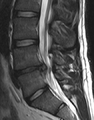

الانزلاق الغضروفي القطني

تحدث الانزلاقات الغضروفية القطنية في الظهر، وغالبًا ما تكون بين الفقرتين القطنيتين الرابعة والخامسة أو بين الفقرة الخامسة والعجز. وهنا يمكن الشعور بالأعراض في أسفل الظهر والأرداف والفخذ ومنطقة الشرج/الأعضاء التناسلية (عبر العصب العجاني)، وقد تنتشر إلى القدم و/أو إصبع القدم. العصب الوركي هو العصب الأكثر تأثرًا، مما يسبب أعراض عرق النسا. يمكن أن يتأثر العصب الفخذي أيضًا ويسبب للمريض شعورًا بالخدر والوخز في جميع أنحاء إحدى الساقين أو كلتيهما وحتى القدمين أو شعورًا بالحرقان في الوركين والساقين.[22] غالبًا ما يضغط الانزلاق في منطقة أسفل الظهر على جذر العصب الذي يخرج من المستوى أسفل القرص. وبالتالي، فإن فتق الفقرة القطنية الرابعة والخامسة يضغط على جذر العصب القطني الخامس، فقط إذا كان الانزلاق خلفيًا جانبيًا.[بحاجة لمصدر]